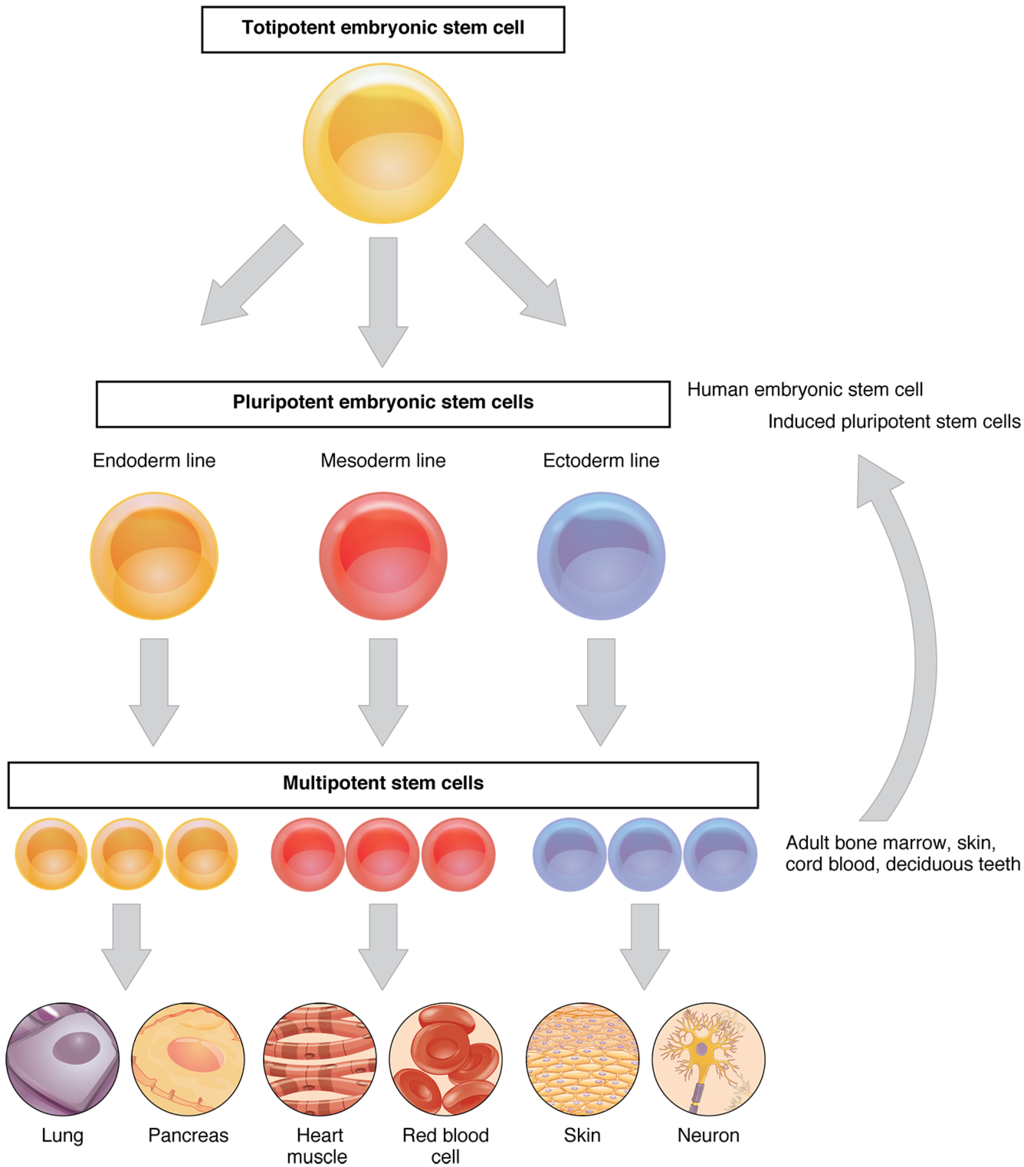

This page is under construction. For now, it is just a resource of the images found in the OpenStax Anatomy and Physiology Handbook. It wil slowly change into a revision tool. Each slide has a number. Use this to refer to the slide. When completed, it will have an unlabelled section, with labelled slides in parallel. On the unlabelled slides, write your answer and use the labelled slide to assess yourself. Keep track by also noting the number on each slide. Improvement at each attempt is important, more so than full marks on a first attempt.